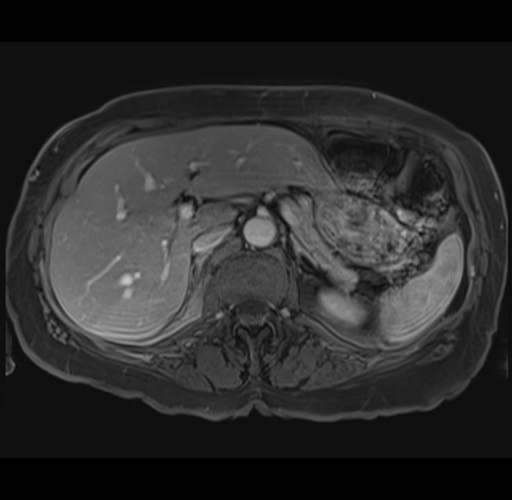

MRI T1